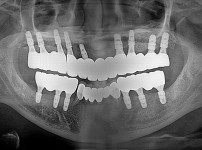

임플란트-전후사진3